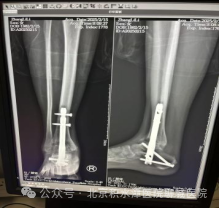

术中影像资料

术后复查影像资料